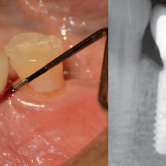

Periimplantitis

La periimplantitis es una infección e inflamación de los tejidos alrededor de un implante dental.

Los pacientes notan que sus encías están inflamadas y sangran alrededor del implante. Esto puede llevar a la pérdida del implante si no se trata.

El tratamiento incluye la limpieza profunda alrededor del implante y, en casos avanzados, cirugía.